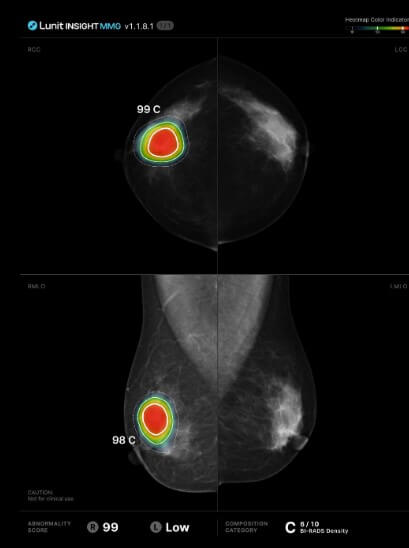

의료AI 대장주 루닛

의료AI 대장주 루닛은 설립 이후 딥러닝 기술 및 AI기술을 통해 인간의 시각적 한계를 보완하는 판독보조 solution을 개발하고 상용화하고 있는 부분이 관심을 받고 있습니다.